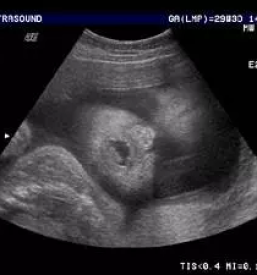

V naši ambulanti se vedno trudimo imeti čimbolj strokoven pristop. To lahko dosežemo le z nenehnim izobraževanjem in spremljanjem razvoja medicinskih postopkov doma ter v tujini. Tako smo se med drugim specializirali za različne preglede, kot je nuhalna svetlina Ptuj.